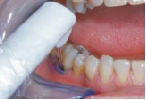

FotoSan 360

Přístroj na principu světlem aktivovaná desinfekce neboli fotodynamická antimikrobiální chemoterapie. Přístroj s okamžitým účinkem ničí veškeré mikroorganismy bez jakýchkoli vedlejších účinků. Jedná se o bezbolestné ošetření, které nevyžaduje anestezii, nemá vedlejší účinky a ničí 99% bakterií. Používá se především v parodontologii a implantologii při léčbě zánětů v okolí zubů a implantátů (dezinfekce tzv. chobotů), záchovné stomatologii (ošetření kazů) i endodoncii (dezinfekce kanálků zubu).